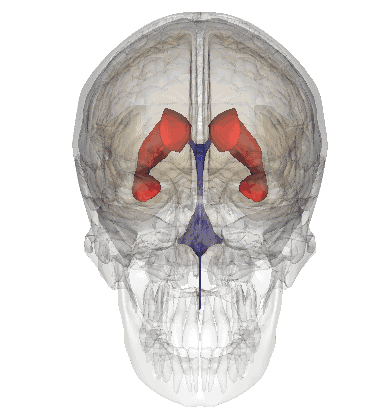

海马和穹窿

hippocampus:海马